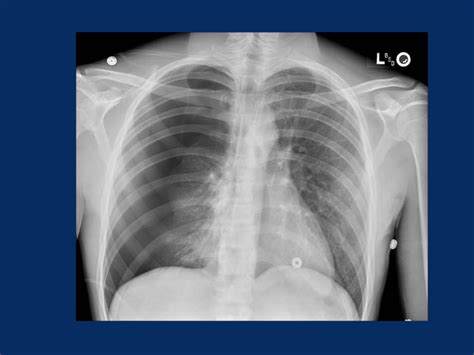

Pneumothorax

Пневмоторакс (Pneumothorax) - ErdeMED